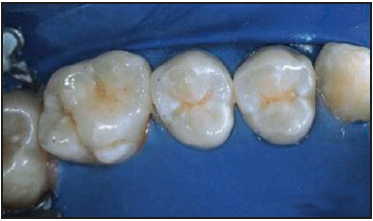

Figure G